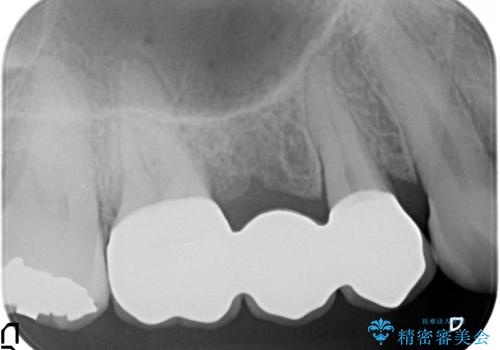

虫歯による歯の喪失 ジルコニアブリッジの製作

- 33万円(仮歯・ジルコニアクラウン×3)費用は治療当時の料金となります

ブリッジは隣の歯を削り、クラウンにしなければならないというデメリットはありますがインプラントと異なり手術をしなくてもよく、入れ歯よりも一般的にしっかりと噛むことができます。